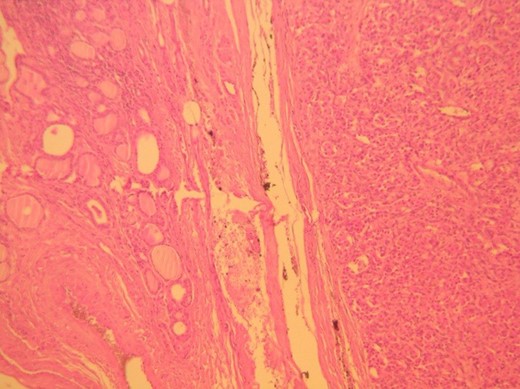

Histologic examination showed a 34 × 26 mm tumor on the left lobe which consisted of neoplastic cells nests arranged in a characteristic ‘zellballen’ pattern (Figs 1 and 2). Immunohistochemistry was positive for neuroendocrine markers (Chromogranin A, Synaptophysin, CD56, NSE, CD 57) and negative for cytokeratins (AE1/AE3, 7, 8, 19), Calcitonin, CEA and Thyroglobulin (Figs 3–5).

Thyroid paraganglioma, Ki67 proliferation marker. Positivity of occasional neoplastic cells.